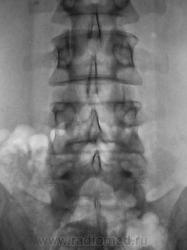

Пациент с болями в пояснице, направлен на рентгенологическое исследование поясничного отдела позвоночника.

А нет ли у него почечной колики справа...и всех делов. Иначе что это за плотные тени в проекции правой почки и в\трети правого мочеточника, артефакты? Касаемо коментариев Юрича - все так и есть, но не маловато ли этого для обращения в клинику, ведь это было и вчера....?

А что там с поперечным отростком L5 справа, и рядом в мягких тканях? Хондрома?

А позвонков разве не 6? И подготовить бы больного. У нас в поликлинике, почемуто не принято готовить больных к съёмке ПКОП,  только если к ЭУ.

Самый начальный деформирующий спондилоз. Листеза нет. Справа несколько небольших теней, могущих быть кокрементами в мочевых путях...

Ничего, Вы себе не нафантазировали, Игорь Иванович. В данном случае "двуконтурности" заднего края отдельных позвонков не избежать, так как на рентгенограмме в прямой стандартной проекции (снимок выполнен стоя), вроде-бы, как-бы намечается некоторое искривление позвоночника во фронтальной плоскости. Конечно, это никакое не искривление, это просто ротация - 1 - 2 позвонков, и становится понятным, что если 1-2 позвонка чуть ротировались, то на ровность заднего контура всех поясничных позвонков расчитывать не приходится.

О ротации, также свидетельствует различная длина поперечных отростков одноименного позвонка, и это видно.